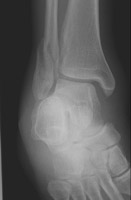

The Weber classification is used to determine the severity of tibiofibular ligament injury by the level of fibular fracture. The Weber B fracture consists of a fracture of the fibula near the joint and a transverse fracture of the medial malleolus (or disruption of the deltoid ligament). This results in partial disruption of the tibiofibular ligament complex and is from supination-lateral rotation injury.

- Click on the image for a larger versionBMortise radiograph of the ankle. The fracture is seen to arise at the same level of the tibiotalar joint, indicative of a Weber B injury.